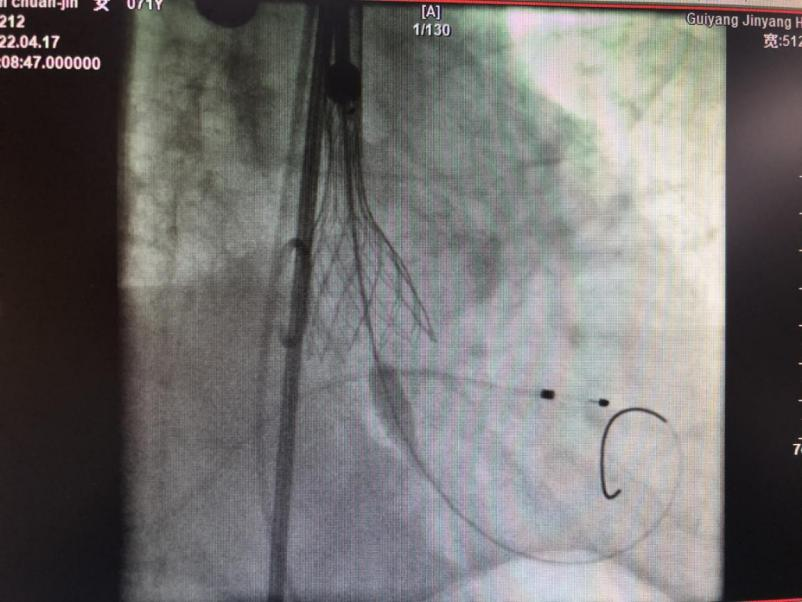

▲TAVR介入手术过程

在多学科的协助下,心内科唐峰博士诊疗团队历经2个多小时,顺利为患者完成经导管主动脉瓣置换术(TAVR)。术后田阿姨恢复良好,顺利出院,她激动的说到“走路不累了,哪里都好了,没想到不开胸也能捡回一条命!”